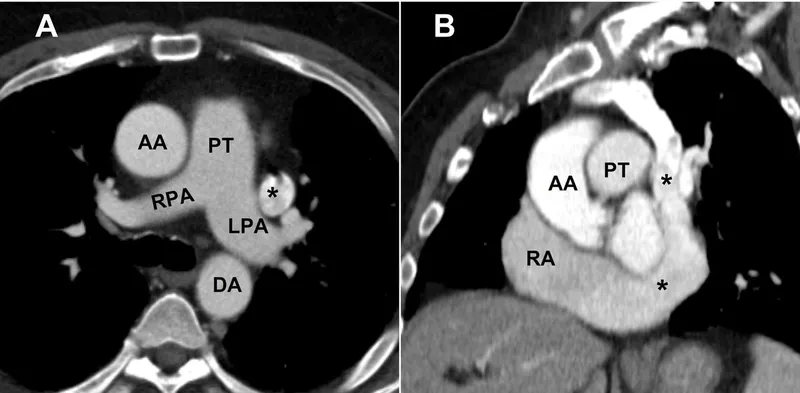

- Level T5-T8: Visualizes all four cardiac chambers, pericardium, and great vessels (ascending/descending aorta, pulmonary trunk).

- Key Structures:

- Heart: Right ventricle (most anterior), left atrium (most posterior).

- Hilum: Pulmonary arteries, veins, and main bronchi bundle together.

- π RALS: Right pulmonary Artery is Anterior to bronchus; Left is Superior.

β The transverse pericardial sinus, located posterior to the aorta and pulmonary trunk, is a critical landmark for surgeons to clamp the great vessels during cardiac surgery.